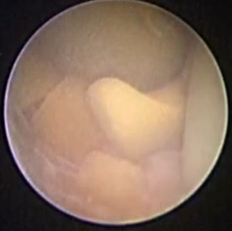

图四:正常的精囊内部管腔

图五:精囊内结石(血精常见病因之一)